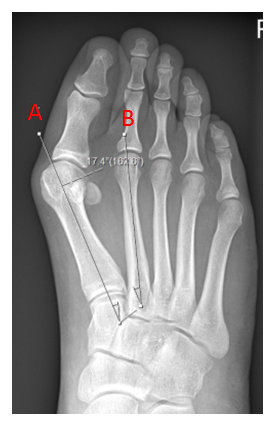

This X-ray shows a significant bunion (hallux valgus) only. The first metatarsal (a) in isolation has drifted away from the second (b)

This X-ray shows a bunion, however the metatarsus adductus angle is significant, reflecting the medial drift of the first three metatarsals towards the inside of the foot. Now the bunion cannot be corrected by just addressing the first metatarsal alone.